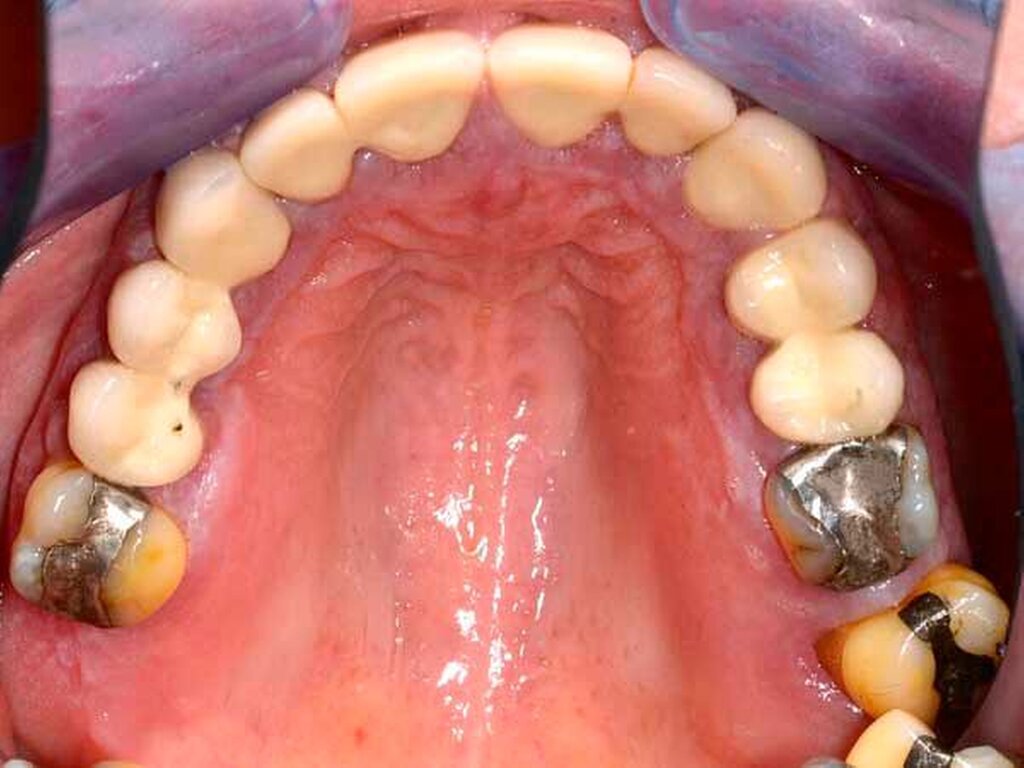

Anamnese: Die 53-jährige Frau stellte sich im Januar 2015 in der Poliklinik für Parodontologie des Universitätsklinikums Dresden vor. Sie war von ihrer Hauszahnärztin mit der Bitte um Diagnostik und Therapie der gingivalen Größenzunahmen (Abbildungen 1a bis 1e) überwiesen worden. Die Patientin gab an, dass die Vergrößerung der Gingiva vor ungefähr einem Jahr begonnen habe und diese sie mittlerweile in ihrer häuslichen Mundhygiene einschränke. Die Benutzung von Hilfsmitteln zur Interdentalraumpflege sei nicht mehr möglich und die Gingiva blute seitdem häufig. Den Kaukomfort ihres 2009 angefertigten Zahnersatzes empfand sie als gut. Als Grund für die multiplen endodontischen Therapien und die Überkronungen an den Zähnen 15, 13 bis 22 sowie 24 und 25 gab die Patientin starke Abrasionen an. Seit dem Auftreten der Gingivawucherungen ergänzte sie auf Anraten ihrer Hauszahnärztin die häusliche Mundhygiene einmal täglich mit Chlorhexidingel, 1-prozentig.

Befund: Bei der klinischen Untersuchung zeigten sich vestibulär und oral im Bereich der Papillen und der befestigten Gingiva generalisierte Gingivawucherungen im Oberkiefer (OK) und im Unterkiefer (UK). Die Interdentalräume waren aufgrund der Gingivawucherungen nicht für Hygienehilfsmittel durchgängig. Der Parodontale Screeningindex (PSI) wies im OK die Codes 3/3/4, im UK die Codes 3/1/3 auf. Der daraufhin erhobene Parodontalstatus (Abbildung 2) zeigte im OK Sondierungstiefen bis 7 mm mit Furkationsbeteiligungen Grad I (Zähne 16, 26, 27). Im UK betrugen die Sondierungstiefen bis zu 4 mm. Die Zahnbeweglichkeit an den Zähnen 16, 26 (Grad I) und 27 (Grad II) war erhöht.

Der Plaqueindex PCR betrug 72 Prozent [O`Leary TJ et al., 1972] und der gingivale Blutungsindex GBI 75 Prozent [Ainamo J et al., 1975]. Das alio loco angefertigte Orthopantomogramm (Abbildung 3) zeigte horizontalen Knochenabbau bis zu einem Drittel der Wurzellänge in beiden Kiefern. Die Zähne 16 und 26 wiesen einen Knochenabbau > 2/3 der Wurzellänge auf. Am Zahn 27 mesial erreichte der Knochenabbau die Wurzelspitze; zudem war der Zahn elongiert und wies eine Kippung nach distal auf. In einer ersten Einzelzahnprognose wurden alle Zähne mit Ausnahme von Zahn 27 als sicher eingestuft. Prothetisch war die Patientin im OK mit einer Brücke (13 bis 15), Kronenblöcken (21/11, 21/22, 24/25) und Amalgamfüllungen an den Zähnen 16 und 26 sowie im UK mit einer geschiebeverankerten Modellgussprothese versorgt.